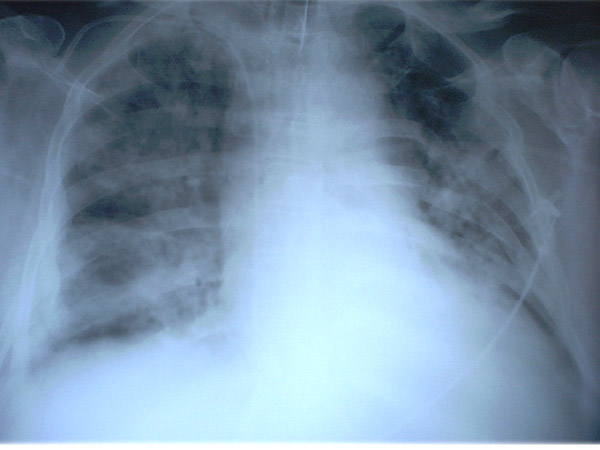

MO Distres respiratorio del adulto por trauma.